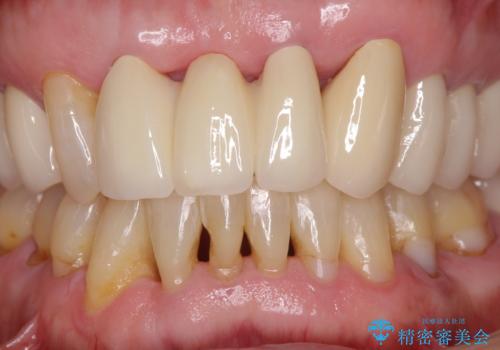

内側に倒れているため、下顎と強く干渉することが懸念されましたが、無理のない咬み合わせで、形態も左右対称に近い状態で仕上げることができました。